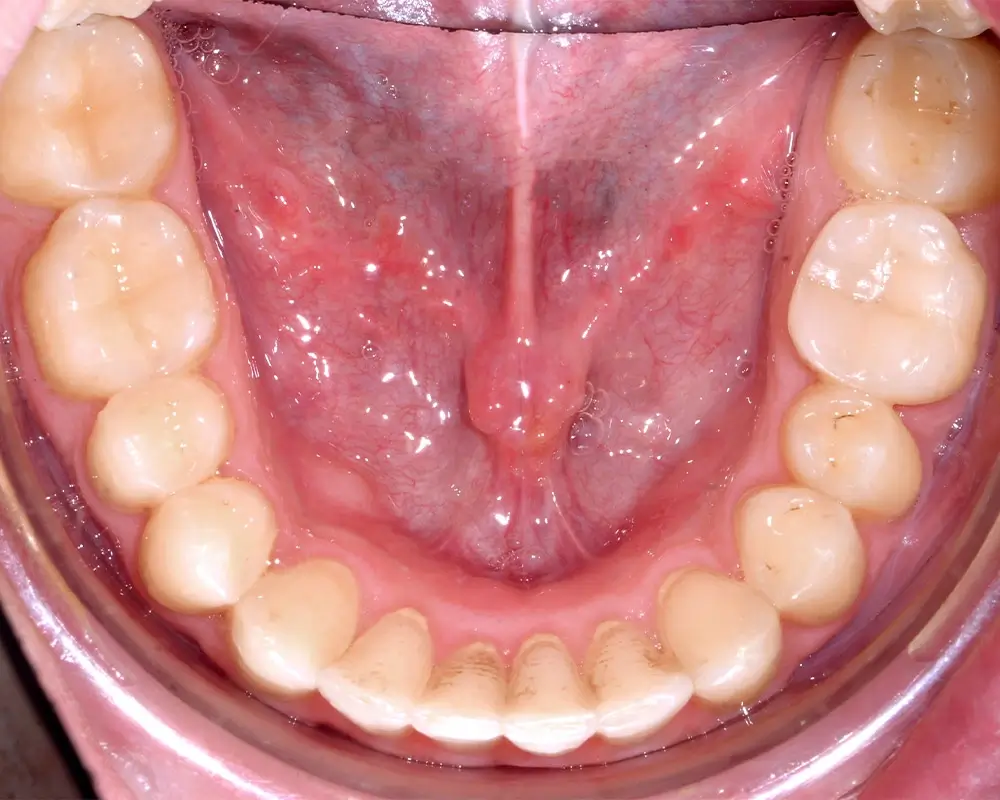

Перекрестный прикус - Кейс 5

Эффективность устранения дефекта прикуса посредством элайнеров FlexiLigner.

27

Количество кап НЧ

25

Количество кап ВЧ

Результаты лечения